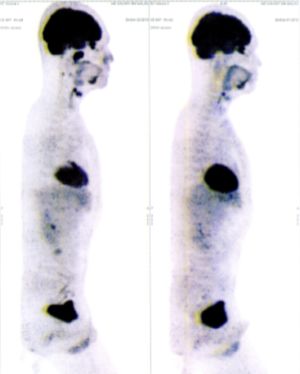

CASE NO: 6 (BREAST CANCER)

A middle-aged women treated for breast cancer now presents with massive liver metastases and a few bone metastases. She refused conventional chemotherapy and came to see us. After just 2 treatment, most of the cancer went into remission and those remaining are less active. Treatment will continue until complete remission.

CASE NO: 7 (BREAST CANCER)

A middle-aged woman treated for breast cancer now presents with bone and liver metastases. After a few treatment, most of the cancer went into remission, and the remaining ones are less active.